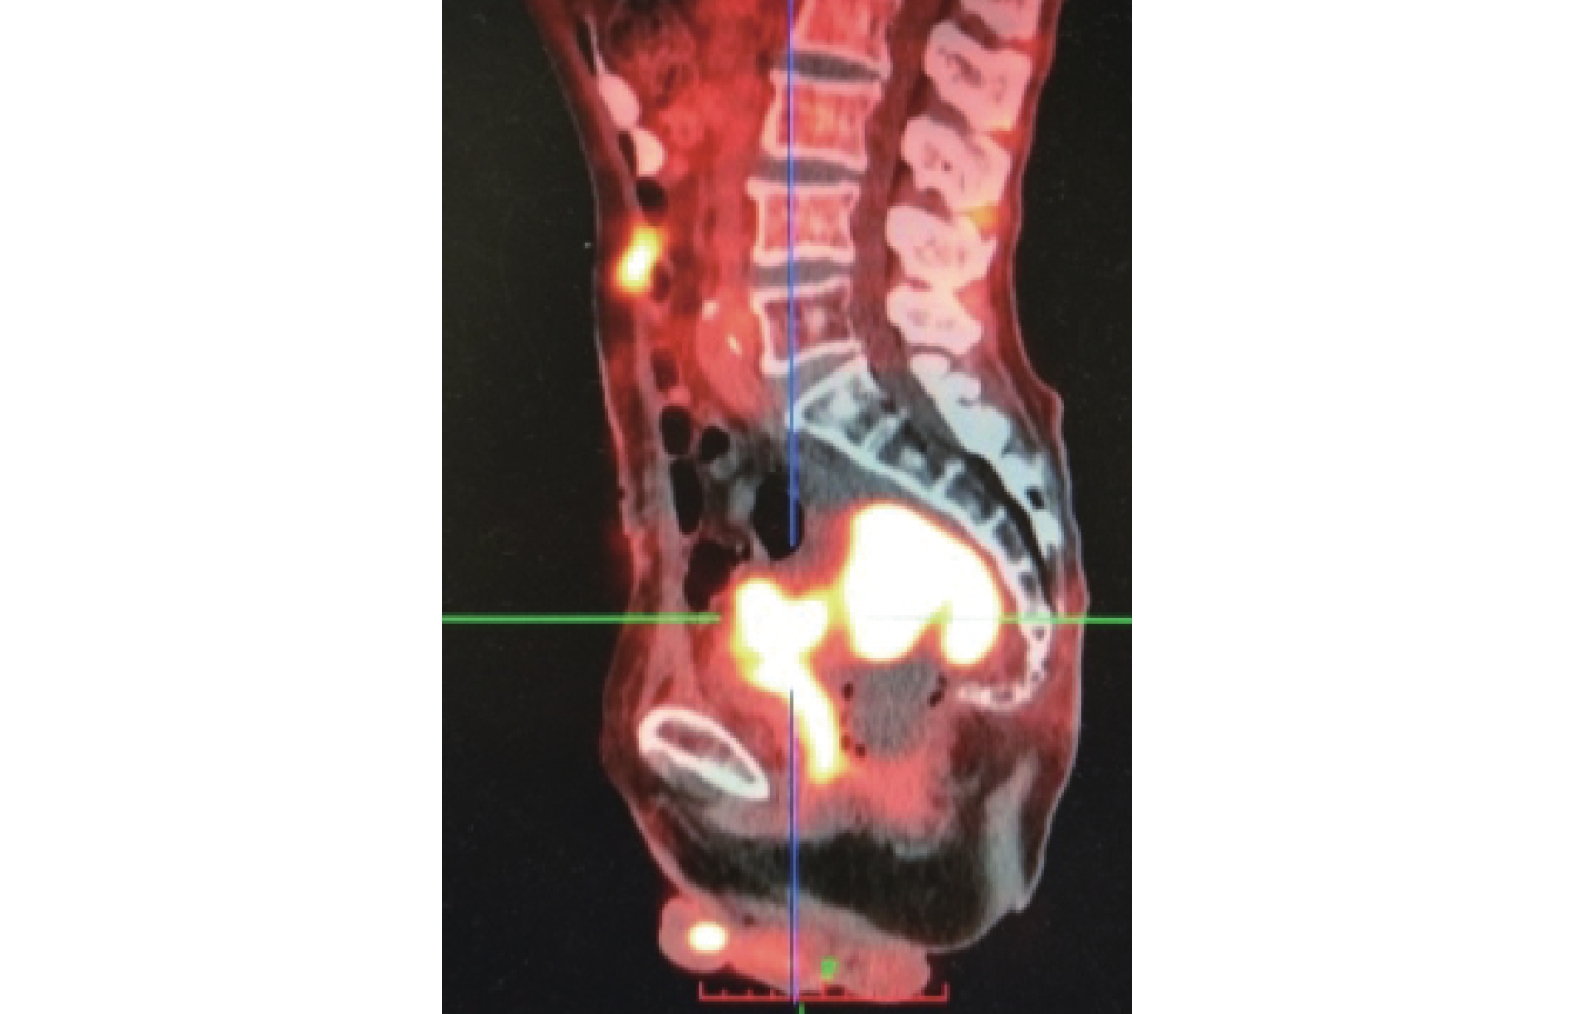

病例 3,病史較長,有下腹部隱痛合并尿路感染,CT 及腸鏡檢查見乙狀結腸及降結腸多發憩室(圖 3a),PET-CT 提示乙狀結腸-膀胱及乙狀結腸-直腸間多發條索樣含氣代謝增高灶,乙狀結腸壁多發代謝增高灶,傾向瘺管合并炎癥可能性大。消化道造影提示乙狀結腸憩室炎、憩室穿孔伴竇道形成(圖 3b),但尿路造影見膀胱充盈良好。考慮結腸憩室穿孔形成慢性炎性粘連,最終導致結腸膀胱瘺。

病例 1,經多學科討論后,先于膀胱鏡下行右側輸尿管支架置入術,術后肛門溢液較前明顯減少,但右腎積水逐漸加重,且肛門溢液再次增多,3 個月后又行右側經皮腎造瘺術,效果良好。術后 5 個月時行 PET-CT 檢查提示盆腔、腹壁多發腫瘤轉移(圖 5)。